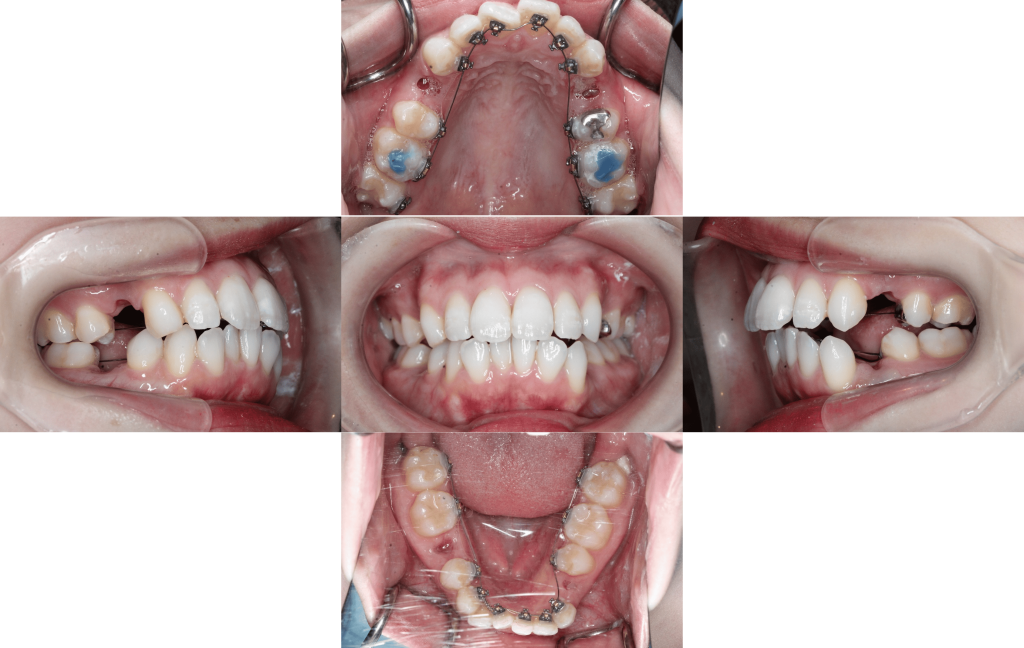

初診

装置装着